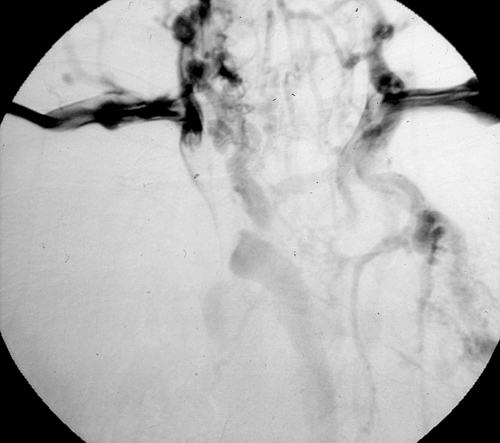

Contraindications to surgical resection and replacement include the presence of SVC syndrome related to unresectable tumors, a completely obstructed SVC with a rich collateral vein circulation and abnormal walls of the proximal vein(s) (i.e., tumor involvement at the margins); particular attention needs to be directed to patients undergoing induction chemo-radiotherapy.

![]() |

| Figure 4. Superior vena cavography showing obstruction by a mediastinal tumor. |

The preoperative work–up should always include total body CT scan for patients with lung cancer or tumors of the mediastinum. Other specific investigations should be tailored according to the histological diagnosis. Superior vena cavography should be performed when SVC invasion is suspected (Figure 4). Alternatively, magnetic resonance imaging can help to define the site and extension of the infiltration and the presence of thrombosis, and anatomical variations of the SVC system can be revealed. Echocardiography should be routinely included to rule out extension of a thrombus into the right atrium. Brain CT scan with contrast injection should always be performed for staging purposes (lung cancer) and also to rule out the presence of any brain disease that may be exacerbated by CNS edema during SVC clamping.